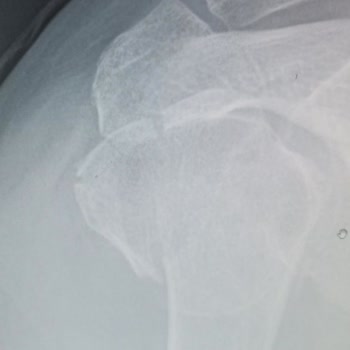

23/09/2025 saat 20:00 civarında Gaziosmanpaşa özel Şafak Hastanesi acil servisine karın ağrısı ve gaz sıkışması şikayetiyle başvurdum. Ancak burada yanlış tedavi uygulandı. İki kolumda da damar yolu açılırken damarlarım patlatıldı. Şikayetim dışında EKG, kan testi ve enfeksiyon testi yapıldı, ayrıca...